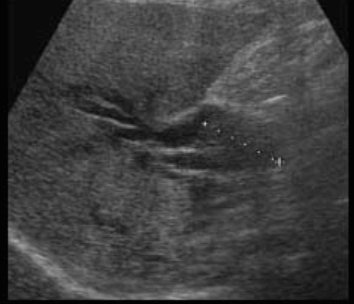

Choledocholithiasis US finding

- 총담관 내에 후방음향음영을 동반한 강한 에코가 관찰된다.

- 총담관의 확장 소견이 보인다. ( 7mm 이상)

- 담석이 관찰되지 않고 간외, 간내담관의 확장소견을 시사하는 엽총징후(shotgun sign)이나 평행관 징후(parallel channel sign)가 관찰되기도 한다.

- 엽총징후(shotgun sign): 간외 담관이 확장되어 간외 담관과 문맥이 이웃해 관찰된다.

- 평행관 징후(parallel channel sign): 간내 담관이 확장되어 인접하고 있는 문맥과 나란히 2개의 관상구조로 나타난다.